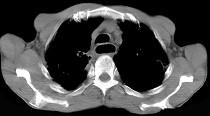

问题 女性患者,67岁进行性吞咽困难半年,X线及CT检查如图,应诊断为 ( )

选项 A.食管癌 B.食管憩室 C.食管炎 D.食管良性狭窄 E.食管静脉曲张

答案 A